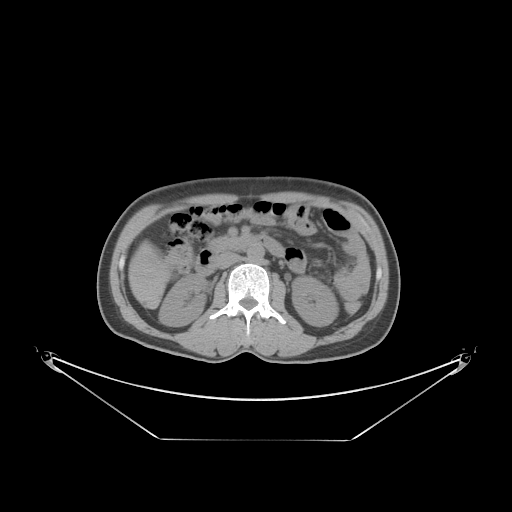

Case Study 3: Multi-Organ Segmentation

The cognition of artificial intelligence is important for computer-aided diagnostic. Multi-organ segmentation can help the machine understand the structure of the human body, which is very important for all the relevant tasks. Therefore, some research has focused on single- or multi-organ segmentation tasks, such as the liver([79, 80]) and the pancreas([81, 82]). In this case study, we use a VNet-based neural network to solve the multi-organ segmentation challenge, SegTHOR, [83]. The SegTHOR challenge includes about 40 CT images of the chest, and aims at the segmentation tasks of the heart, aorta, trachea, esophagus, and further more.

As Fig. 11 shows, The workflow of this case study includes six parts: “input”, “pre-processing”, “dataset management”, “neural network”, “visualization”, and “analysis”. The “input” includes images of the chest and annotations.

“Pre-processing” rescales the range of the image values with a window width and a window level. Then, the input images are re-sampled with the “resample” tool to change their size. The “dataset management” function subsequently splits the dataset into a training and a testing set randomly, yet reproducibly.

“Neural network” employs VNet to train and validate the model, which can be used to segment organs from the chest. Then, the segmented images can be visualized via the “organ visualization” option, and the results can be analyzed with the “result analysis” tool to generate an MS-Excel based report.

VI-3 Result and Visualization